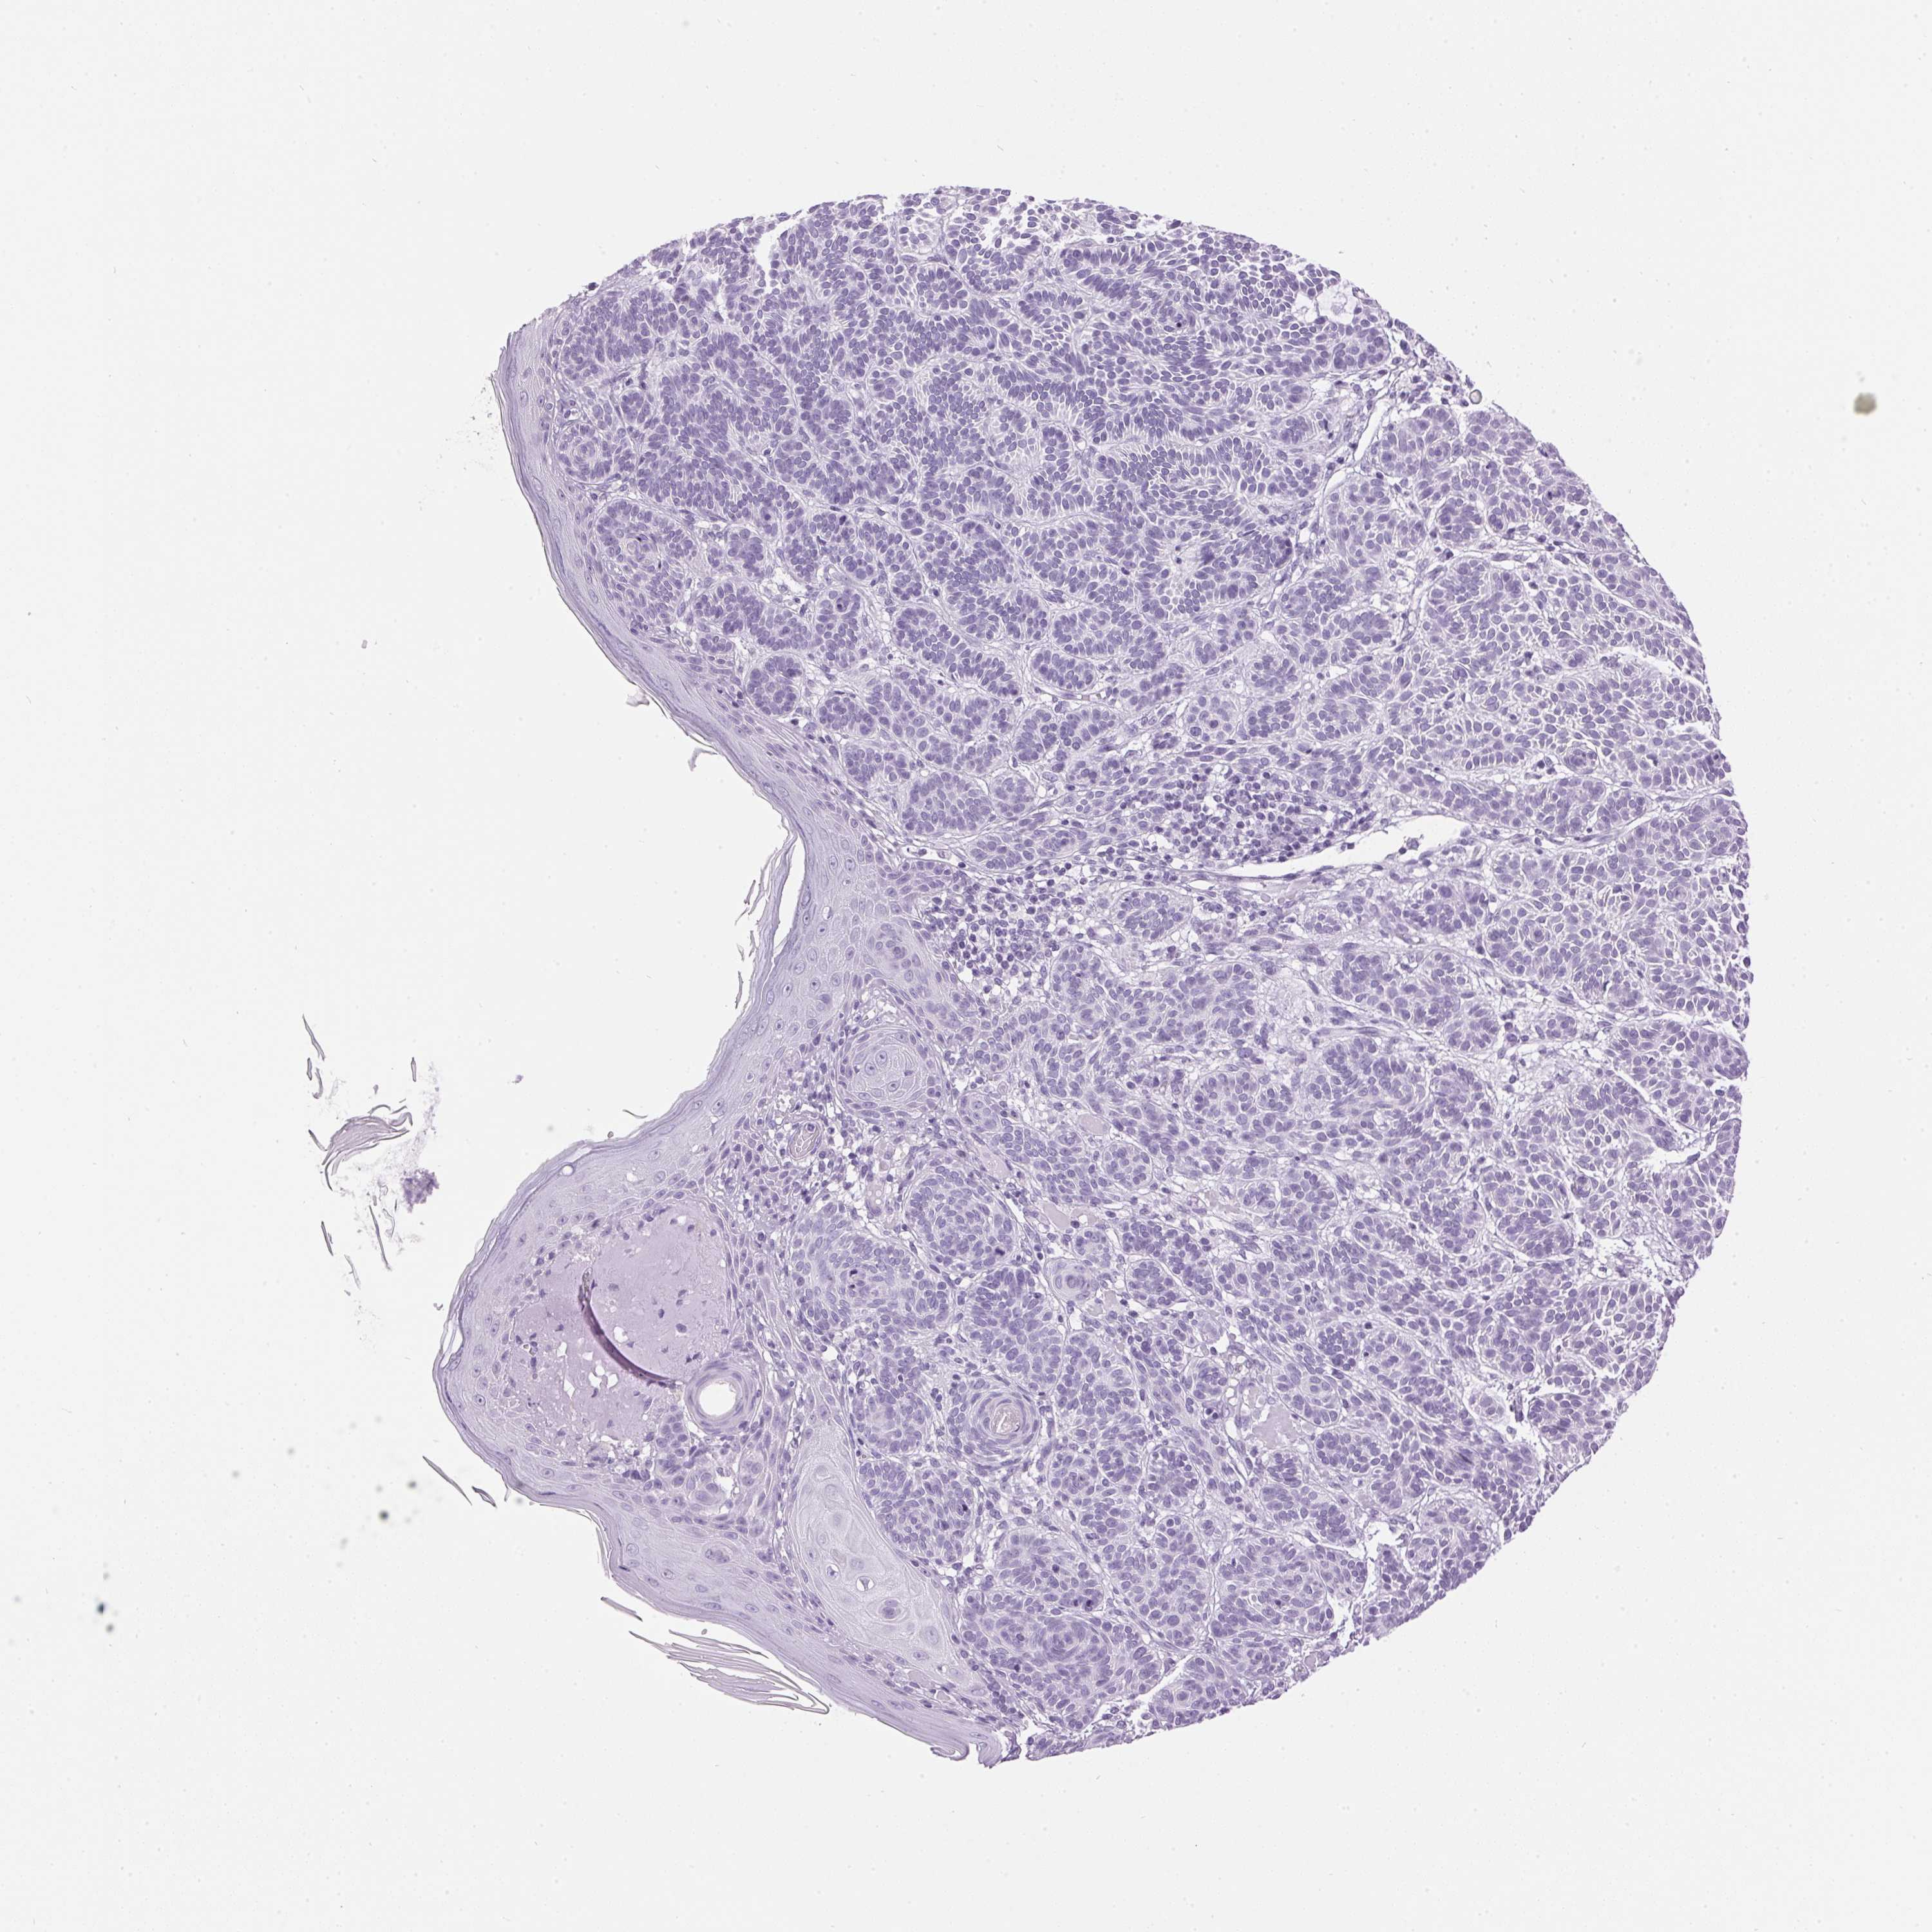

SKIN CANCER - Protein expressioni

A mouse-over function shows sample information and annotation data. Click on an image to view it in a full screen mode. Samples can be filtered based on level of antibody staining by selecting one or several of the following categories: high, medium, low and not detected. The assay and annotation is described here.

Antibody staining in the annotated cell types in the current human tissue is reported as not detected, low, medium, or high, based on conventional immunohistochemistry profiling in selected tissues. This score is based on the combination of the staining intensity and fraction of stained cells.

Each image is clickable and will lead to virtual microscopy that enables deeper exploration of all samples and also displays staining intensity scores, fraction scores and subcellular localization as well as patient and tissue information for each sample.

Antibody HPA063202

Staining

High

Strong

Quantity

Location

Basal cell carcinoma